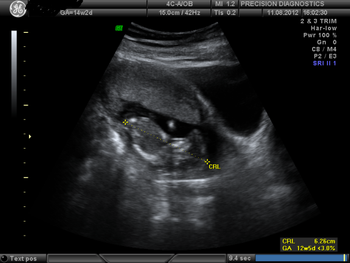

A 25-year-old woman was referred for routine antenatal scan at 14 weeks, 2 days of pregnancy.